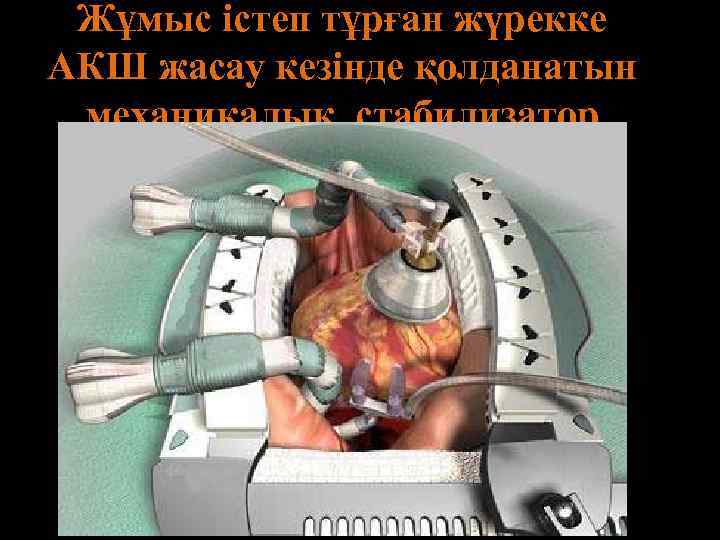

Жұмыс істеп тұрған жүрекке АКШ жасау кезінде қолданатын механикалық стабилизатор

Жұмыс істеп тұрған жүрекке АКШ жасау кезінде қолданатын механикалық стабилизатор